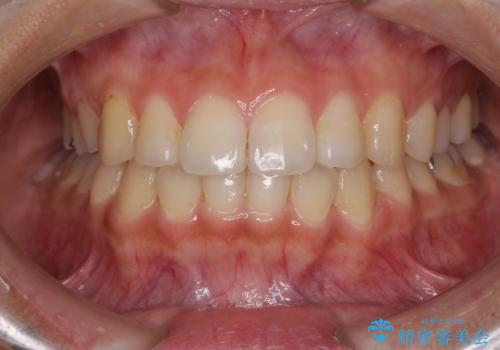

前歯の突出感とデコボコ インビザラインで改善

右上の小臼歯は歯根癒着をしており、様々な方法を試みるも動かすことができませんでした。

それでも奥歯のかみ合わせに不自由はなく、歯列をきれいに整えることができました。